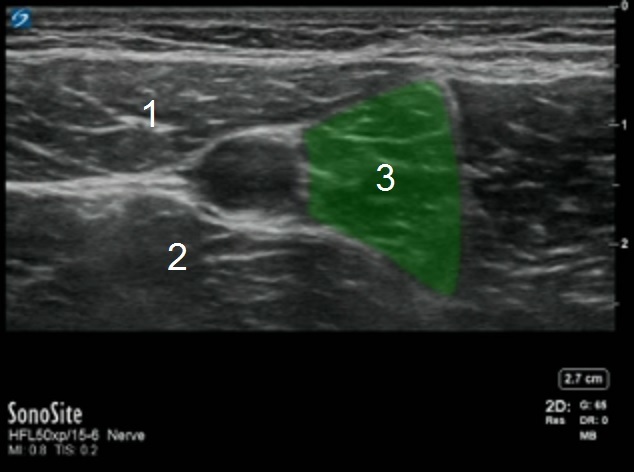

Adductor Muscular Boundaries Image

Sartorius Muscle

Vastus Medialis Muscle

Adductor Longus